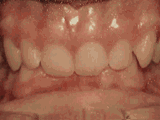

第六种

深覆合,咬牙时,上牙盖住下牙的部位过多,影响美观,经过矫正的牙齿是这样的